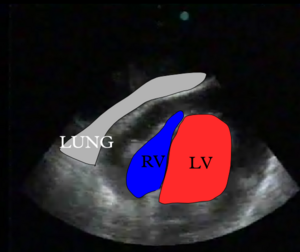

Left parasternal long axis

Image showing the left parasternal long axis transection (PSLAX) of the heart by the ultrasound waves